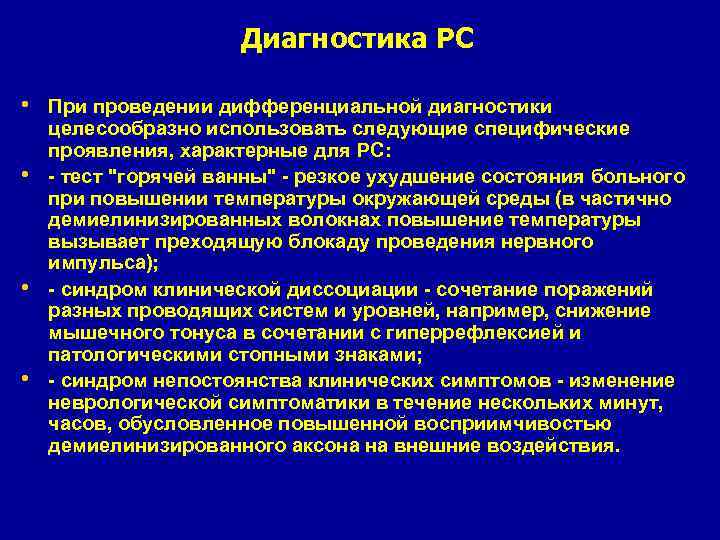

Диагностика PC • При проведении дифференциальной диагностики • • • целесообразно использовать следующие специфические проявления, характерные для PC: - тест "горячей ванны" - резкое ухудшение состояния больного при повышении температуры окружающей среды (в частично демиелинизированных волокнах повышение температуры вызывает преходящую блокаду проведения нервного импульса); - синдром клинической диссоциации - сочетание поражений разных проводящих систем и уровней, например, снижение мышечного тонуса в сочетании с гиперрефлексией и патологическими стопными знаками; - синдром непостоянства клинических симптомов - изменение неврологической симптоматики в течение нескольких минут, часов, обусловленное повышенной восприимчивостью демиелинизированного аксона на внешние воздействия.

Диагностика PC • Диагностика PC основывается в первую очередь на клинических проявлениях. Одним из основных критериев является сочетание "рассеянной" симптоматики, обусловленной многоочаговым поражением белого вещества (т. е. выявление не менее двух отдельно расположенных очагов в белом веществе мозга, которые возникли не одновременно), и волнообразного течения заболевания (чередование обострений и ремиссий или колебания скорости прогрессирования). • При проведении дифференциальной диагностики целесообразно • • • использовать следующие специфические проявления, характерные для PC: - тест "горячей ванны" - резкое ухудшение состояния больного при повышении температуры окружающей среды (в частично демиелинизированных волокнах повышение температуры вызывает преходящую блокаду проведения нервного импульса); - синдром клинической диссоциации - сочетание поражений разных проводящих систем и уровней, например, снижение мышечного тонуса в сочетании с гиперрефлексией и патологическими стопными знаками; - синдром непостоянства клинических симптомов - изменение неврологической симптоматики в течение нескольких минут, часов, обусловленное повышенной восприимчивостью демиелинизированного аксона на внешние воздействия.